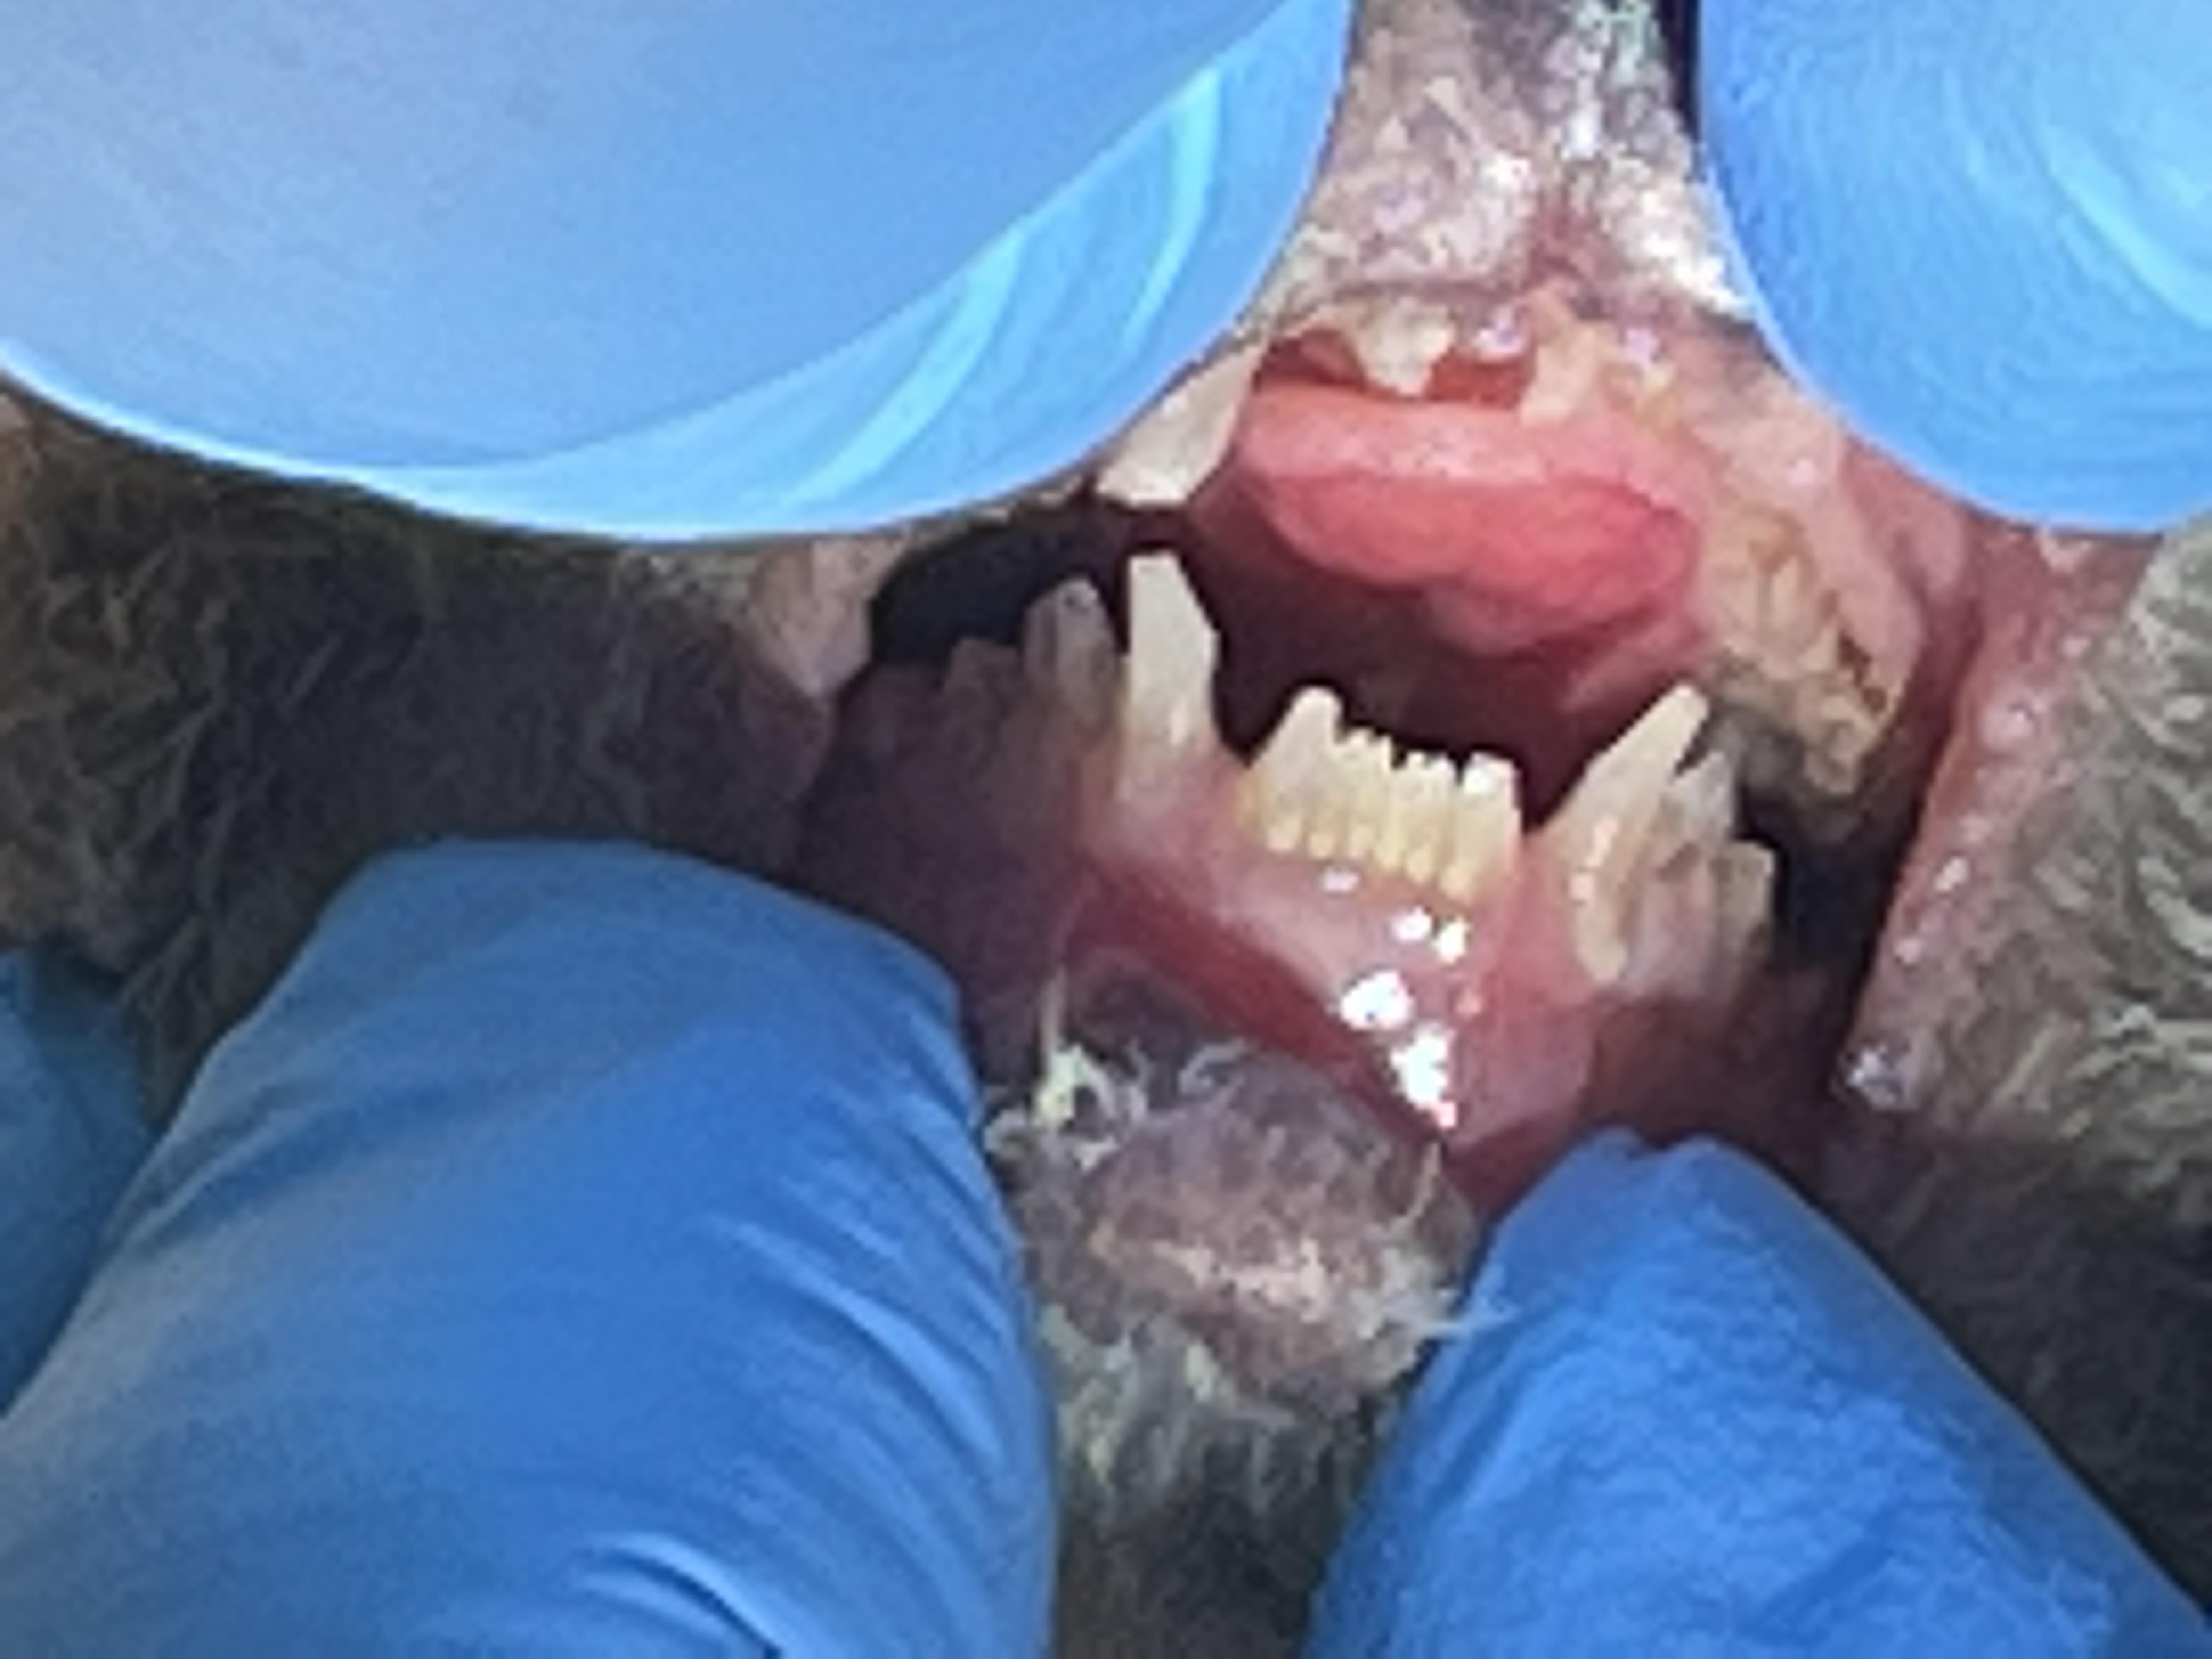

Cotton Top Tamarin

A 2022 Cotton Top Tamarin maxillary canine endodontic procedure is an example of successful endo case that avoided a surgical extraction for this very small patient. A working length radiograph revealed with file in place at 11 mm. showed that the file had gone beyond the apex. 8mm. was chosen as the proper working length and the endo procedure was completed. See fill radiograph.